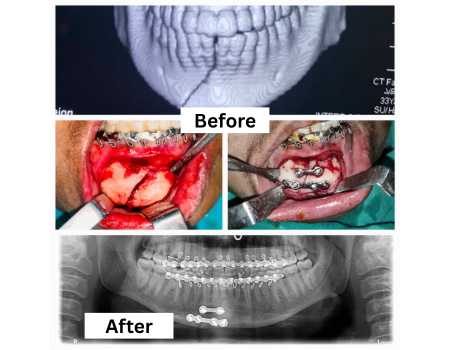

Orthognathic Surgery

Orthognathic surgery corrects jaw and lower face structure, growth, and airway issues like sleep apnea and TMJ disorders , malocclusionproblems due to skeletal disharmonies.